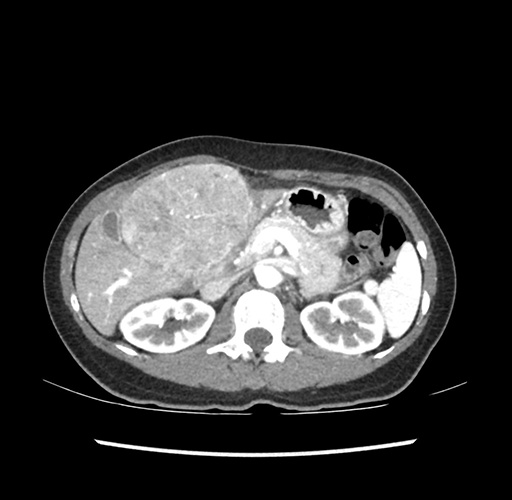

Imaging Analysis

Look through the patient's CT scan to identify any areas of concern for the necessary procedure.

Based on your CT findings, which issue(s) would give reason for "planned slowing down moment(s)" in this case?

Considering a standard left lateral sectionectomy procedure, what step(s) of the operation would you do differently in this case ?